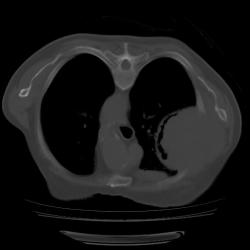

Правое легкое: в проекции средней доли (S3,4,5) определяется объемное образование преимущественно однородной структуры с ровными, четкми контурами размерами 92х88х94мм. Плотность его составляет 19-25 едН. В медиальных отделах образования содержится серповидная полоска воздуха. Латеральные отделы образования выходят за контуры грудной полости на 42 мм. На этом участке ребра не дифференцируются. Внутренний контур передней зубчатой, подлопаточной мышц размытый, граница между образованием и ними отчетливо не видна. Кзади от образования, в кортикальных отделах в легочной ткани инфильтрация. Кпереди от описанного образования расположен участок, широким основанием прилежащий к грудной стенке, имеющий плотность 12-20 ед.Н, однородную структуру, размеры 14х48мм. Прилежащее ребро интактно.